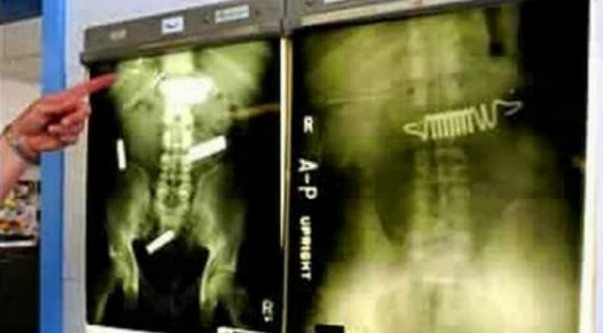

insan-ameliyat-esya89- Pil ve yatak yayı

Tutuklular, hastaneye gidebilmek ya da hapishaneye kaçak olarak sokabilmek için bazen çok acayip şeyler yutabiliyor. Amerika’nın Kuzey Karolina eyaletindeki bir hapishanede bulunan tutuklular, hastaneye gönderilme umuduyla pil ve yatak yayı yutmuşlar. Her iki tutuklu da denemesinde başarılı oldu; yukarıda, karın ağrısı şikayetiyle gittikleri hastanede çekilen röntgenleri görüyorsunuz.